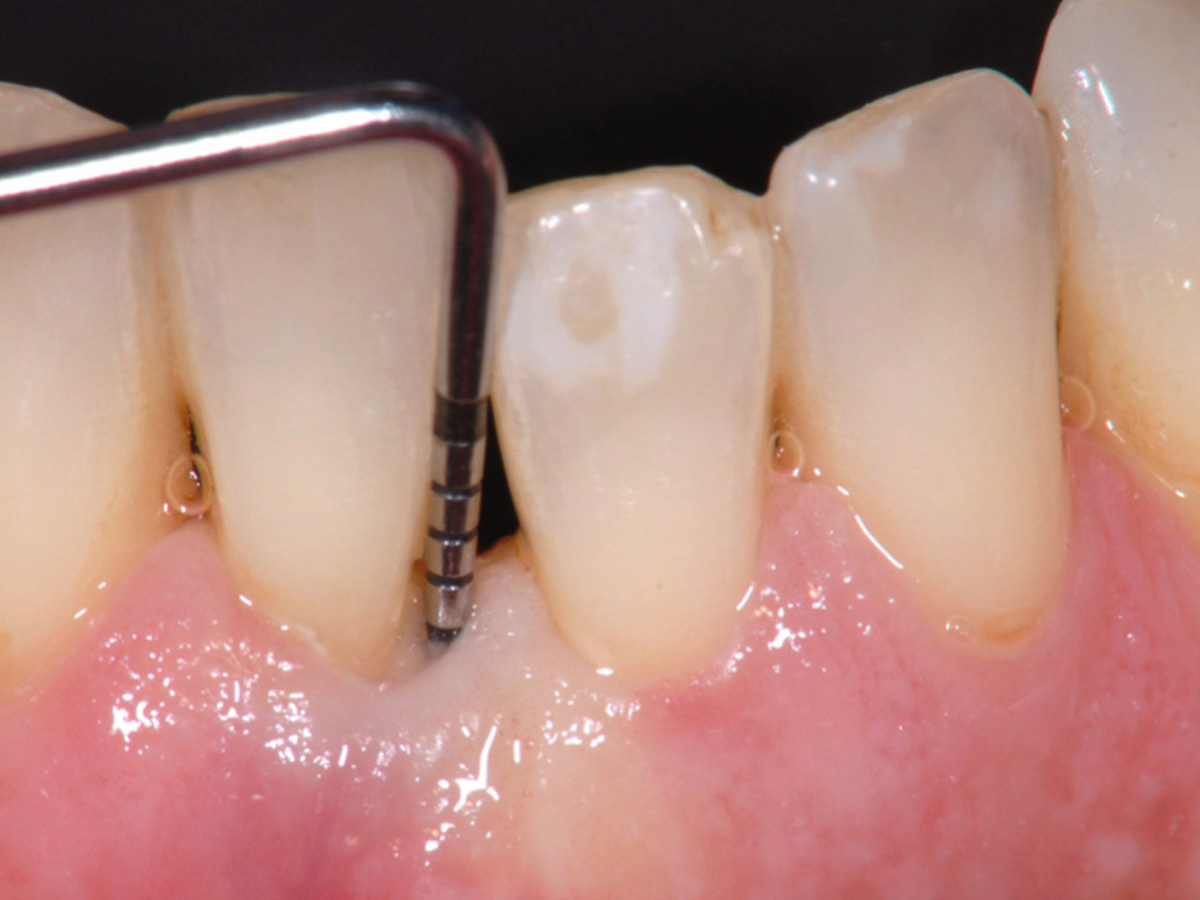

Nach der nicht-chirurgischen Parodontitis-Therapie verbleiben an stark parodontal-kompromittierten Zähnen häufig noch Resttaschen, die im Rahmen einer erfolgreichen Parodontitis-Therapie weiter behandelt werden müssen. Zu diesem Zeitpunkt stellt sich also die Frage, ob der einzelne Zahn mittels parodontalchirurgischer Verfahren erhaltungsfähig ist oder doch besser extrahiert werden sollte. Regenerative parodontalchirurgische Verfahren spielen an dieser Stelle eine große Rolle. Doch wann sollte welche chirurgische Technik, wann sollten welche regenerativen Materialien verwendet werden? Der Workshop vermittelt Kenntnisse, wann ein Zahnerhalt mittels Regeneration parodontaler Defekte erfolgreich möglich ist und wann welche chirurgischen Techniken und regenerativen Materialen zielführend sind.

HANDS-ON

Die Teilnehmer trainieren am Tiermodell verschiedene mikrochirurgische Techniken der Parodontalchirurgie. Zusätzlich werden die Schritte regenerativer Maßnahmen an unterschiedlichen Defekten (z.B. an 1-, 2- und 3-wandigen Defekten) mit den verschiedenen regenerativen Materialien geübt.